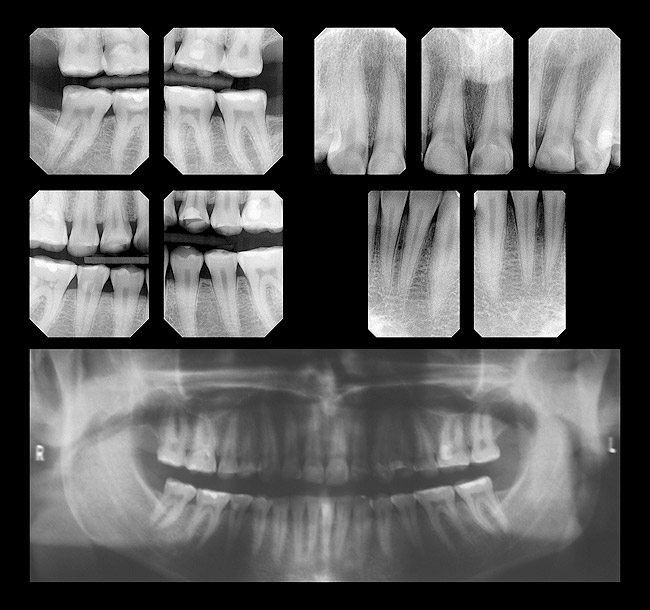

Diagnosticul, evaluarea riscului şi prognosticul

PARODONTAL. Pe baza datelor clinice şi radiologice, pacienta a fost încadrată în tipul II de afectare parodontală, conform clasificării AAP (fig.2). Măsurătorile parodontale decelează adâncimi ale şanţurilor gingivale de 3mm sau mai mici, cu o uşoară sângerare la atingerea cu sonda. Molarul 3.6. prezintă retracţie gingivală de 1,5mm cauzată de abraziunea prin periaj dentar.

BIOMECANIC. Pacienta prezintă o expunere îndelungată a mediului bucal la acizii gastrici, ceea ce a condus la eroziunea severă a tuturor dinţilor maxilari şi a celor laterali mandibulari (fig. 3,4). Afectarea cea mai severă se observă pe feţele palatinale ale dinţilor frontali superiori (fig.5).

La examenul clinic nu s-a decelat nici un proces carios, însă un număr de obturaţii de compozit de la nivelul dinţilor posteriori sunt deficitare, existând structură dentară erodată în jurul compozitului (fig.6). Impresia clinică sugerează o erupţie compensatorie în asociere cu procesul de eroziune, ceea ce determină ca dinţii să fie în contact în intercuspidare (fig.7).